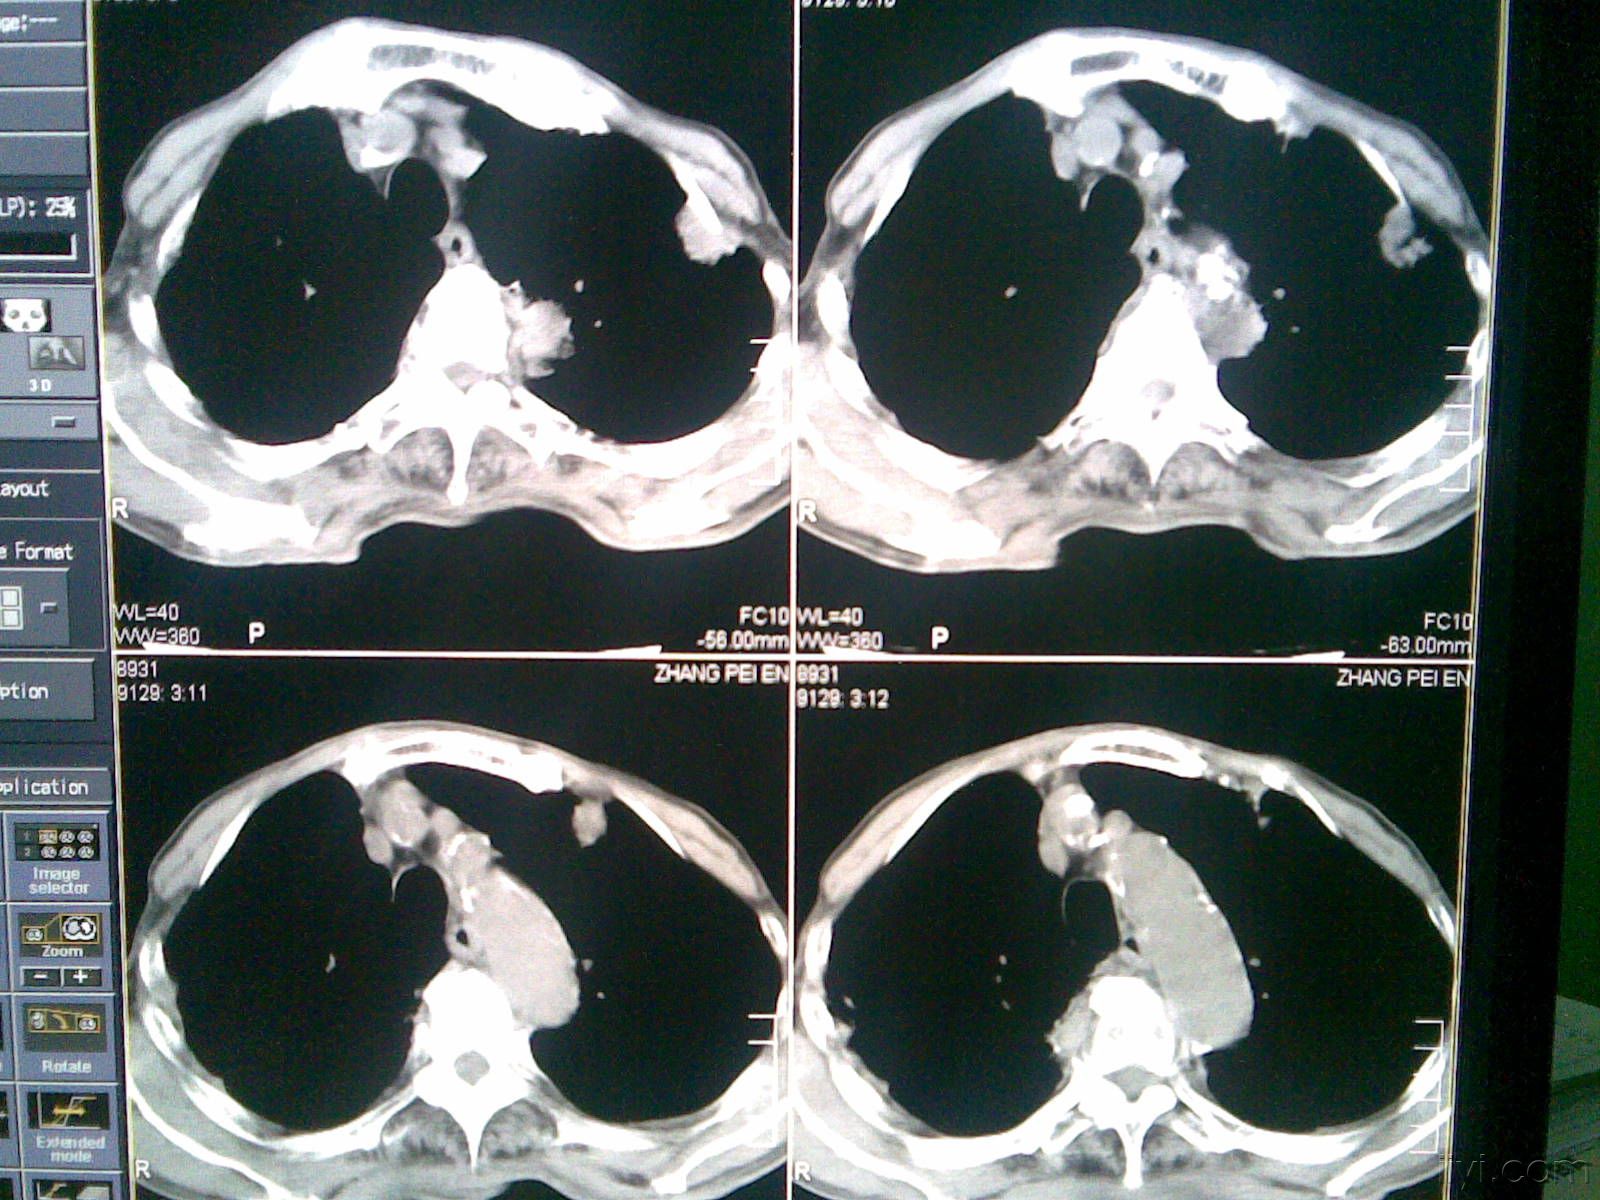

_右肺纖維化CT檢查